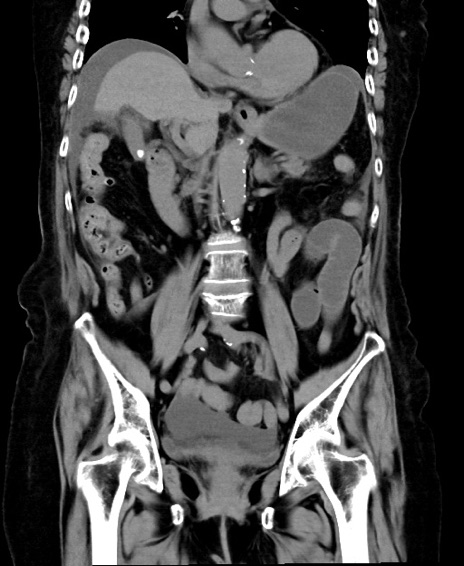

症例40(冠状断像)他院1日前

冠状断像